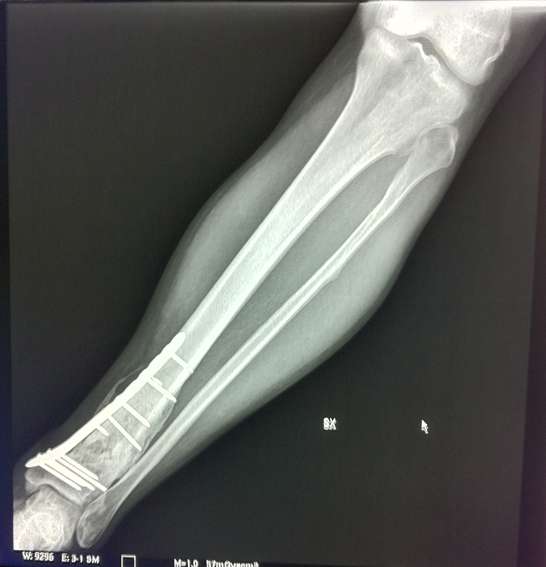

Seconda operazione: rimozione placca rotta e "montaggio" nuova placca:

[​IMG]

Nuova placca

[​IMG][​IMG]

La prima operazione è stata nel 04/2010 (prima piastra)

La seconda nel 10/2010 (sostituzione piastra)

La terza nel 04/2012 (rimozione seconda piastra)